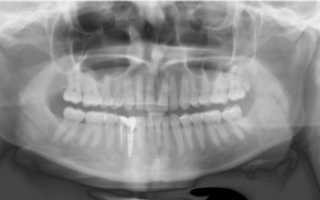

Панорамная рентгенограмма

О состоянии ротовой полости позволяют судить панорамный снимок и компьютерная томография.

Панорамная рентгенограмма показывает состояние височно–нижнечелюстного сустава, гайморовых пазух необходима при планировании операций, имплантации.

Врачи ее назначают пациентам при первичном обращении, чтобы оценить состояние верхней и нижней челюсти. Каждый человек хотя бы раз в жизни должен сделать панорамный рентген.

Панорамная рентгенограмма помогает в ситуациях, когда трудно определить причину боли, особенно при скрытых полостях, больших пломбах и коронках. При разлитой боли пациент может ошибочно указывать на соседний здоровый зуб.

Панорамным называется рентген всех зубов. Движения пациента в процессе проведения исследования сделают снимок нечетким, поэтому голову больного фиксируют, и специальное устройство совершает оборот вокруг нее так, что с одной стороны перемещается трубка, а с другой — плёнка.

Такая процедура назначается пациентам с патологией ортодонтии или травмами нижней челюсти.